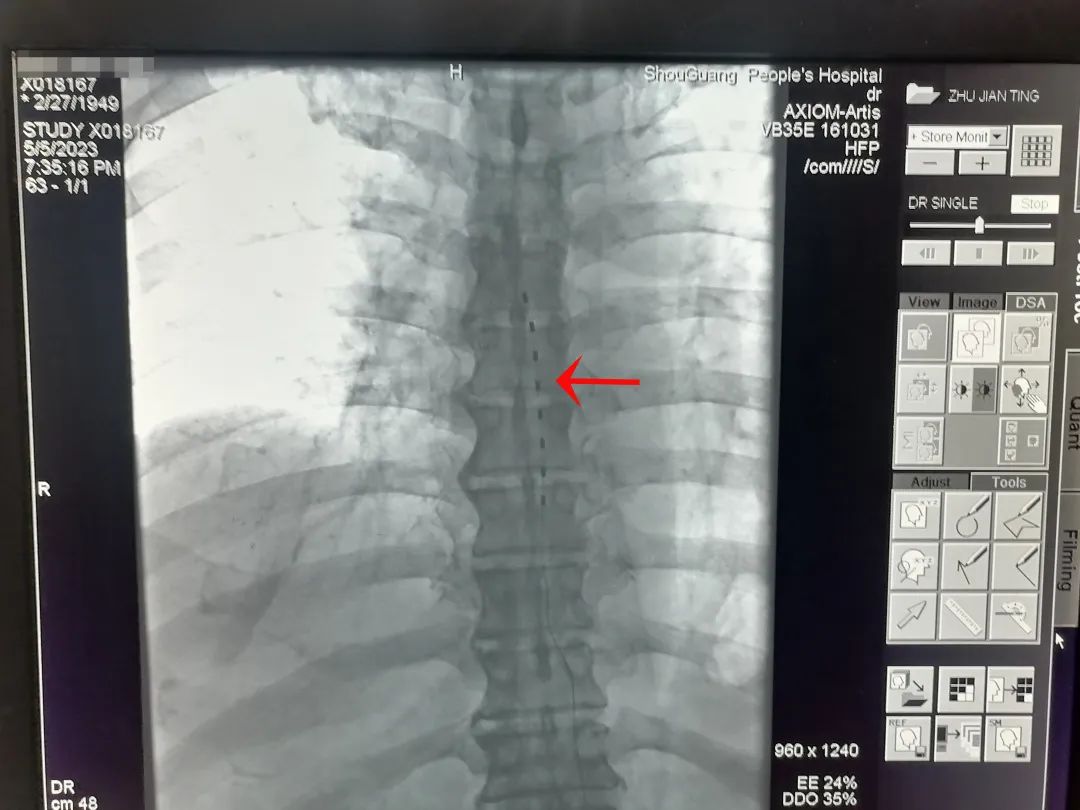

椎管内植入的刺激电极

脊髓神经电刺激疗法是将电极植入脊柱椎管内,以脉冲电流刺激脊髓神经,阻断疼痛信号通过脊髓向大脑传递,使疼痛信号无法到达大脑皮层,从而达到控制疼痛的目的,是目前国际上公认的治疗慢性顽固性疼痛的先进疗法。它的成功开展,为慢性顽固性疼痛患者的治疗提供了一种新的、有效的治疗途径,为此类疾病患者带来了巨大福音,使无数慢性顽固性疼痛患者摆脱了疼痛的困扰。